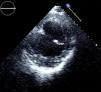

As imagens apresentadas são de um homem de 62 anos, fumador, sem antecedentes de cardiopatia, internado no nosso hospital por pneumonia adquirida na comunidade. A radiografia torácica da admissão mostrava cardiomegalia e o eletrocardiograma tinha ondas Q nas derivações inferiores. O ecocardiograma transtorácico mostrou dilatação ligeira das cavidades esquerdas, depressão severa da função sistólica ventricular esquerda, evidenciando-se uma formação aneurismática envolvendo a porção basal das paredes posterior, inferior e lateral, com 8 cm de diâmetro e que continha trombo (Figuras 1 e 2). Não foi possível, através desta técnica, um diagnóstico diferencial inequívoco entre aneurisma e pseudonaeurisma, pelo que se realizou ressonância magnética, que revelou enfarte inferior antigo extenso, com extensão à porção adjacente do ventrículo direito, com rutura miocárdica na parede inferior. Estabeleceu-se assim o diagnóstico de pseudoaneurisma localizado às paredes inferior e posterior, com trombo organizado no seu interior (Figuras 3 e 4). O cateterismo cardíaco revelou doença de um vaso com oclusão crónica ao nível do segmento médio da coronária direita. Foi proposta correção cirúrgica, que o doente recusou. Manteve-se clinicamente estável em classe NYHA II até ao 10.° mês de seguimento após internamento, tendo posteriormente abandonado a consulta.